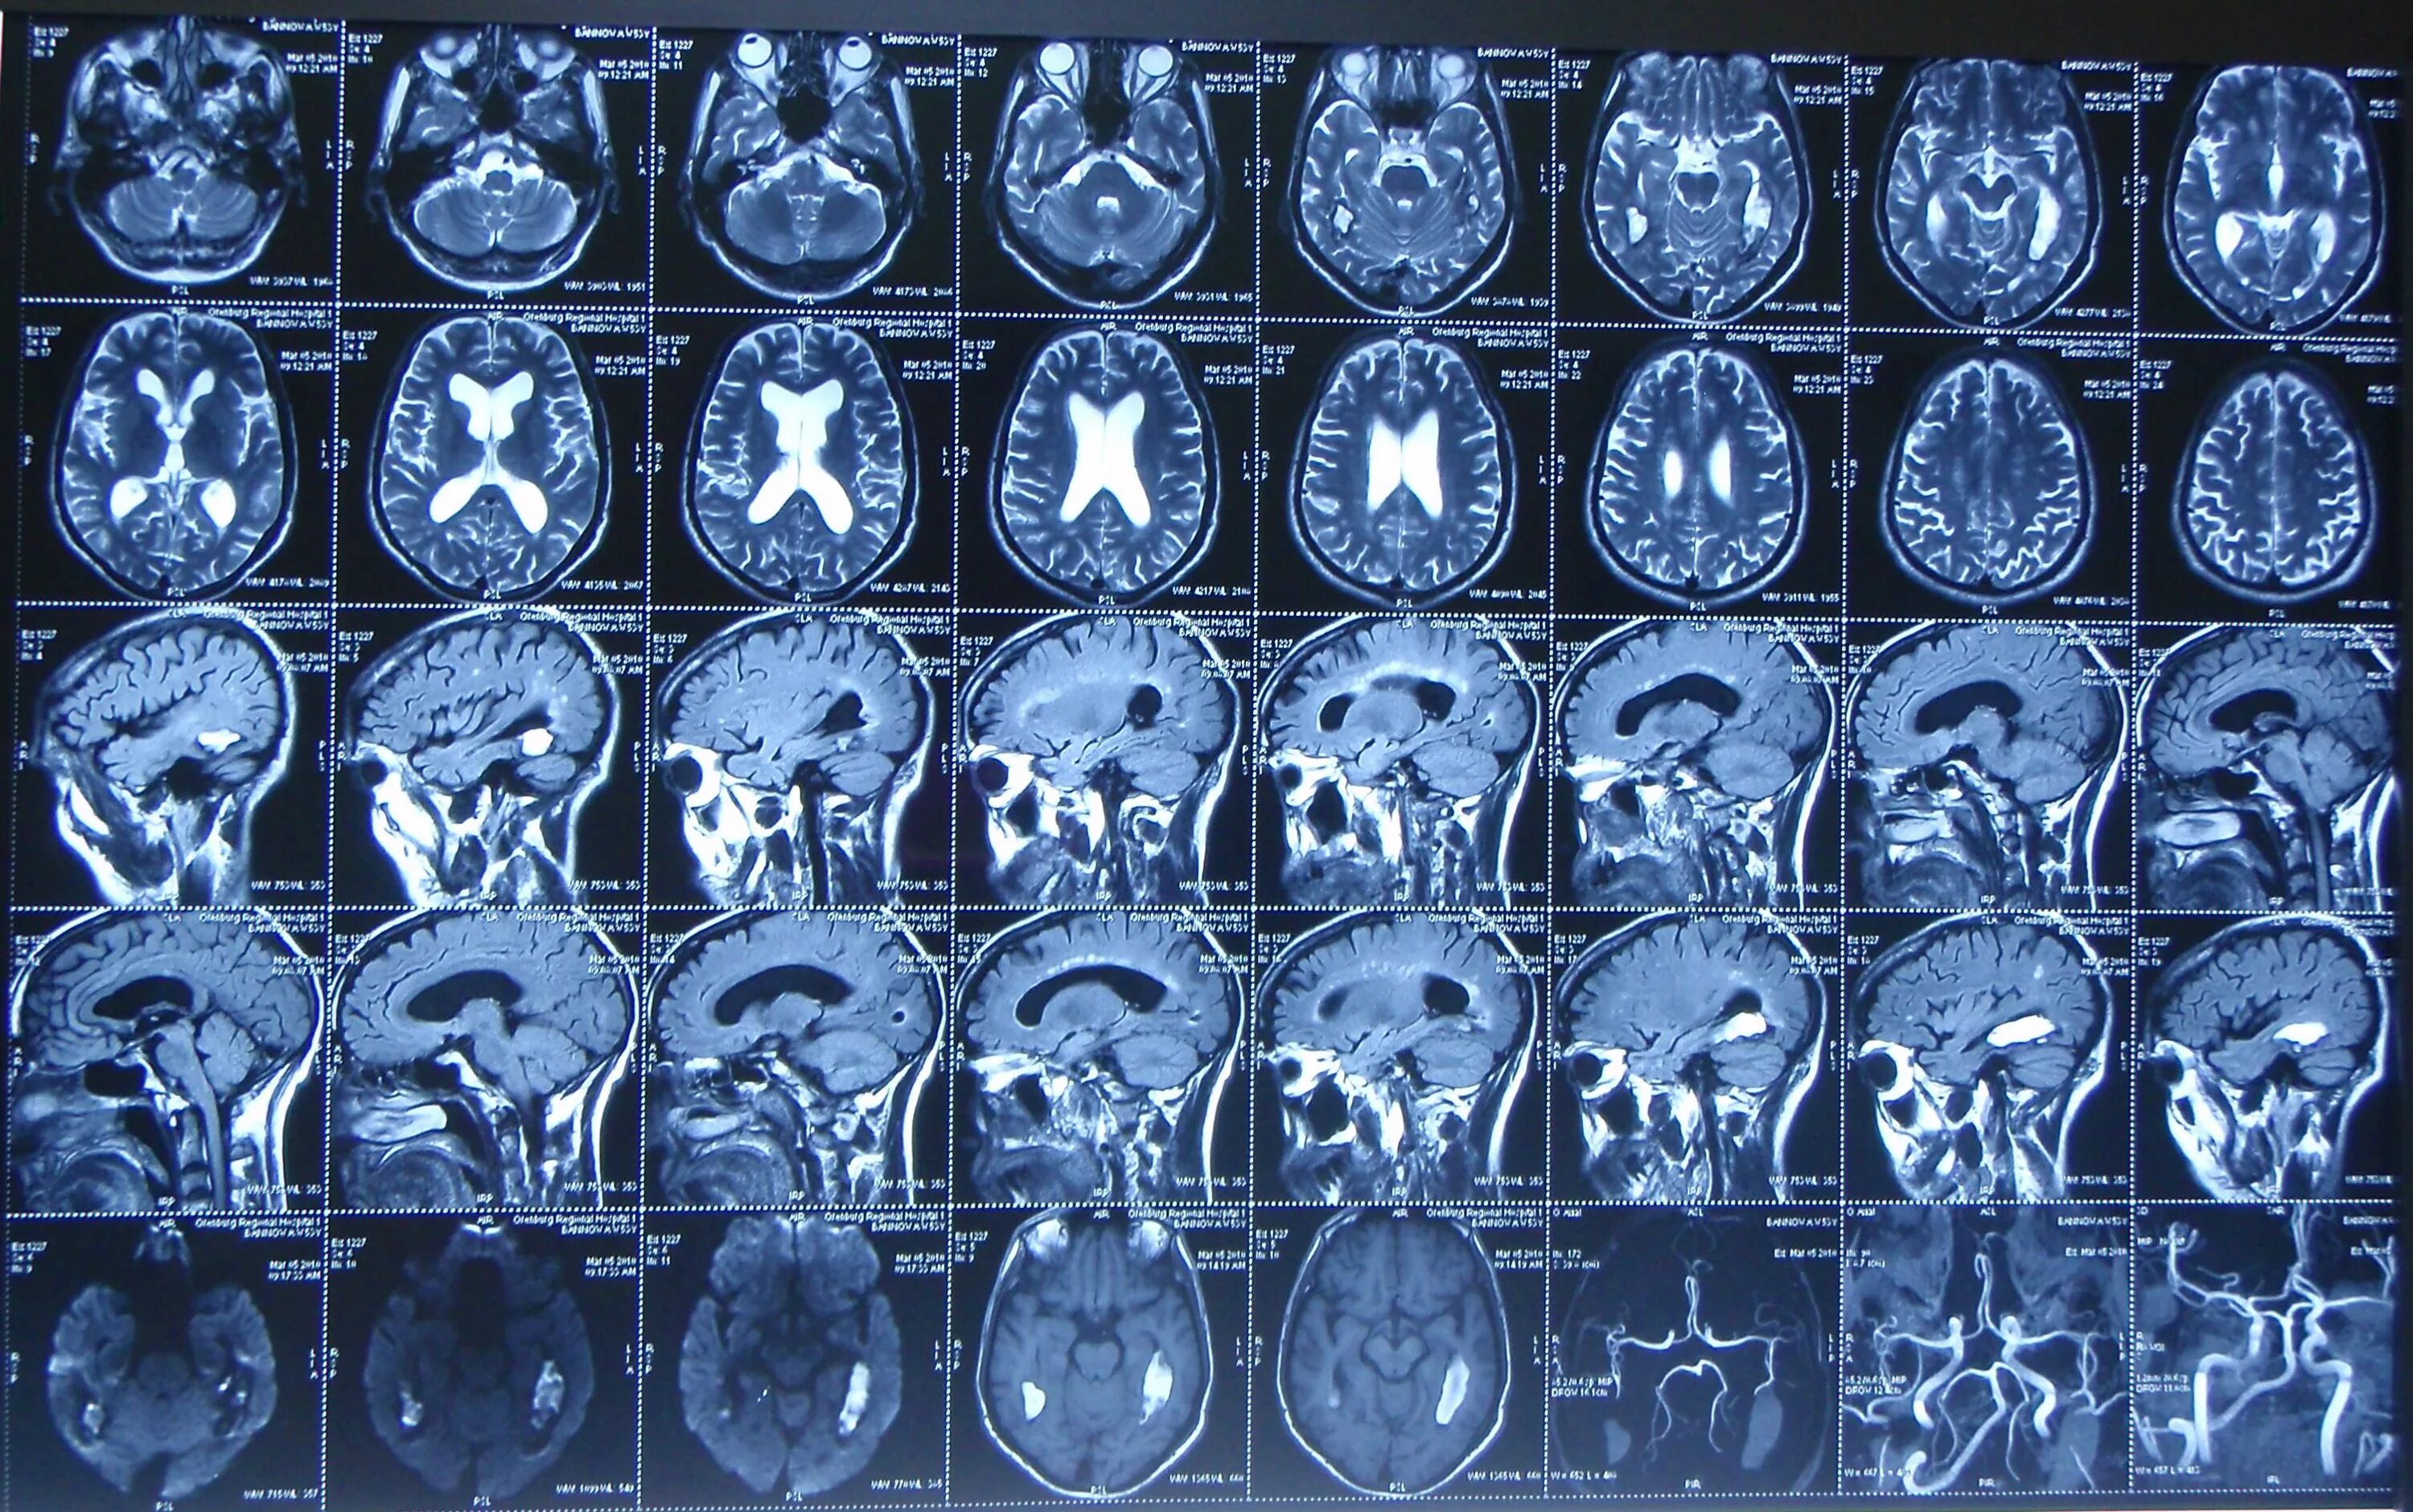

Какие виды кт